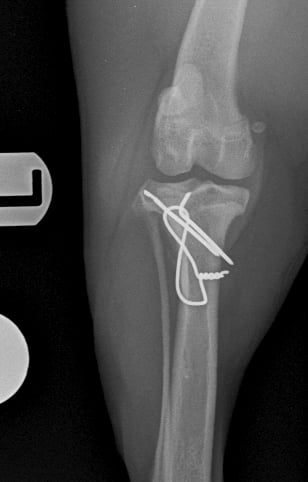

Surgical repair was performed using a medial approach to the proximal tibia. The avulsed tibial tuberosity fragment was identified, anatomically repositioned, and stabilized with two 1.2 mm Kirschner pins and a 1 mm tension band wire (Figs. 3 and 4).

Fig. 4